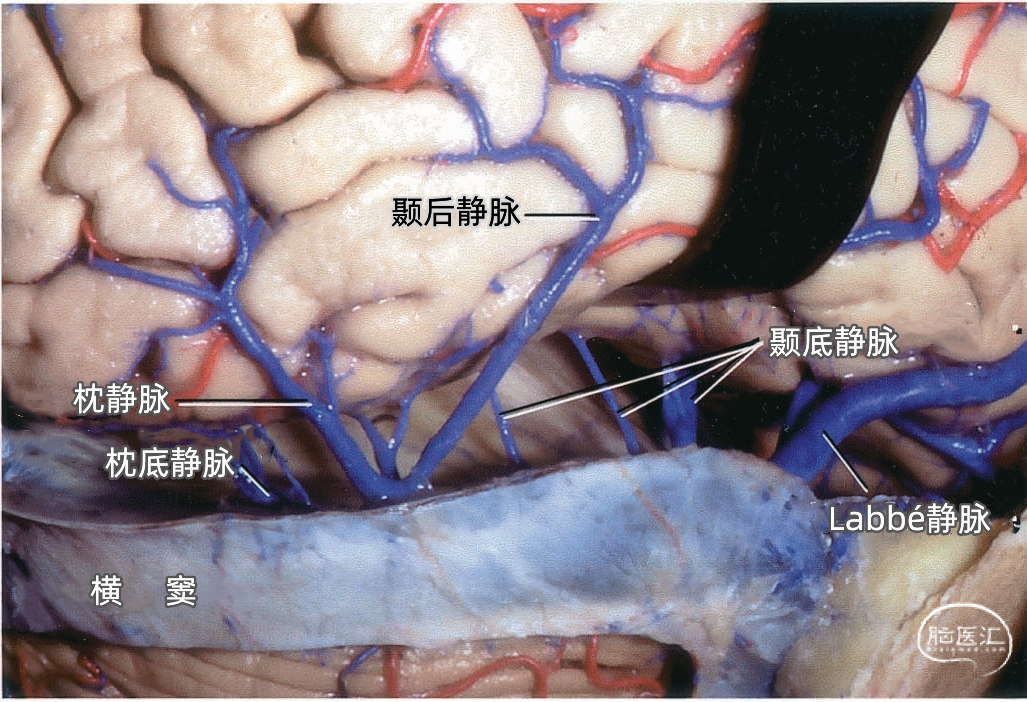

颞叶外侧面的皮层静脉可引流入横窦(上图),但在流入横窦之前,它们常向内沿颞叶底面进入小脑幕的短窦,此窦进入横窦末端之前在小脑幕内走行大约1cm。来自颞叶和枕叶底面的皮层静脉通常汇入外侧小脑幕窦。 Labbé静脉通常终于横窦(上图),但也可弧形围绕大脑半球下缘汇入外侧小脑幕窦。▼9.小脑幕窦

▼2.Labbé静脉

Labbé静脉也称下吻合静脉,是跨越颞叶外侧,连接外侧裂与横窦之间的最大吻合静脉。它通常起自外侧裂中部,行向后下,进入横窦前部。 Labbé静脉经过颞叶表面的位置有可能非常靠后甚至位于颞叶的最后界,或非常靠前达颞叶前1/3的外侧面。在此研究的20例半球中,12例Labbé静脉位于颞中静脉水平,6例位于颞后静脉水平,2例位于颞前静脉水平。有时会有两条Labbé静脉,其中后支通常会粗大一些。

下图示横窦和小脑幕窦的分支。抬起颞叶的后部,暴露进入横窦的Labbé静脉、颞后静脉和枕后静脉,从颞叶底面进入小脑幕窦的颞底静脉。

下图示放大观。从前方暴露Labbé静脉。从后部颞下入路手术,可能牺牲Labbé静脉和来自颞叶、枕叶外侧面的静脉,还可能需要牺牲多条汇入小脑幕窦的颞底静脉和枕底静脉。

颞叶静脉划分为:引流颞叶凸面的外侧组和引流颞叶底面的下组。 颞叶外侧组静脉还分为上升组,行向外侧裂。下降组,注入颞叶下方的静脉窦。上升组由颞外侧裂静脉组成,下降组由颞前、中、后静脉组成。 颞外侧静脉组及其引流区域如下:颞前静脉引流外侧面前1/3,颞上回除外;颞中静脉引流颞叶凸面中部;颞后静脉引流颞叶凸面后1/3,有时包括角回和顶叶前部;颞外侧裂静脉引流从颞极到外侧裂后端的颞上回。 颞下静脉分为:外侧组引流入小脑幕前外侧的窦;内侧组沿颞叶内侧缘,流入基底静脉。外侧组由前、中、后颞底静脉组成,颞底静脉好像放射状从枕前切迹发出,经过颞叶的下面。内侧组由钩回静脉、海马前静脉和颞叶内侧静脉组成。颞极附近基底面通常由颞外侧裂静脉引流。 颞下静脉及其引流区域如下:颞底前静脉引流颞底前1/3、颞枕回和邻近的海马旁回;颞底中静脉引流颞叶下面中1/3;颞底后静脉引流颞叶底面和枕叶前部;钩回静脉引流钩回和邻近的海马旁回:海马前静脉引流钩回后部和邻近的海马旁回;颞内侧静脉引流脑干上部旁基底池边缘的海马旁回。

小脑幕组(上图 绿色)的桥静脉汇入行经小脑幕的静脉窦,即小脑幕窦或小脑幕附近的横窦和岩上窦。本组静脉引流颞叶外侧面和底面、枕叶的底面,包括颞底静脉、枕底静脉和来自颞叶外侧面的降静脉,如Labbé静脉。 除Labbé静脉外,这些静脉虽然有可能进入横窦,但大多数围绕半球的下缘汇聚于枕前切迹到达外侧小脑幕窦。而Labbé静脉通常汇入横窦。大脑底面的桥静脉汇入静脉窦之前,经常粘连于与中颅窝底硬膜和小脑幕表面。 从外侧面引流入小脑幕窦的静脉包括颞前静脉、颞中静脉、颞后静脉和Labbé静脉。

在颞底的后方可能遇到许多桥静脉(下图),这些静脉包括颞、枕、颞底、枕底静脉和Labbé静脉,伤及这些从大脑半球下表面进入横窦和小脑幕窦的静脉,经常会产生某种程度的静脉梗塞和颞叶水肿。这些静脉闭塞以后,有可能导致对侧肢体偏瘫,其中面部和上肢较下肢更明显,优势半球受累还可能导致失语。 在横窦和岩上窦结合部抬起颞叶时经常遇见的难题是有许多来源于颞叶外侧面和底面的静脉聚集在这一区域(上图)。颞下入路手术后遗症的产生往往是因为Labbé静脉的闭塞;但是术中单纯烧闭Labbé静脉的情况并不多,因为当颞下入路需要在颞叶内侧暴露小脑幕缘时,也需要牺牲其他许多这一区域的桥静脉。